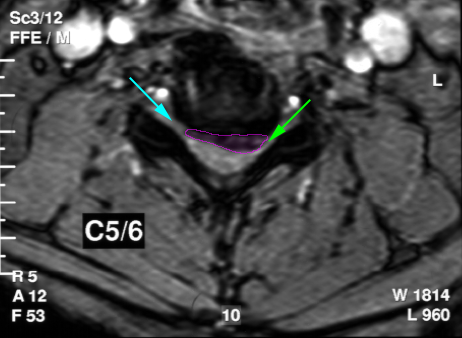

Κήλη αυχενικού δίσκου, επίπεδο Α5-Α6, με στένωση του νευρικού τρήματος (πράσινο βέλος) και πίεση του εξερχόμενου νεύρου. Ελεύθερο τρήμα με κυανό βέλος. |